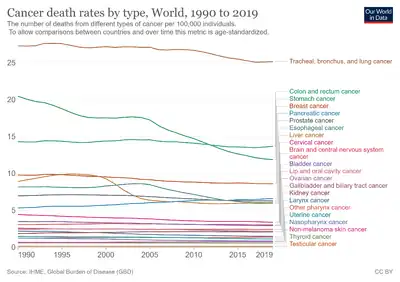

Epidemiology

Globally more than 1 million people get colorectal cancer every year[23] resulting in about 715,000 deaths as of 2010 up from 490,000 in 1990.[148]

As of 2012, it is the second most common cause of cancer in women (9.2% of diagnoses) and the third most common in men (10.0%)[17]: 16 with it being the fourth most common cause of cancer death after lung, stomach, and liver cancer.[149] It is more common in developed than developing countries.[150] Globally incidences vary 10-fold with highest rates in Australia, New Zealand, Europe and the US and lowest rates in Africa and South-Central Asia.[151]

Colorectal cancer is the second highest cause of cancer occurrence and death for men and women in the United States combined. An estimated 141,210 cases were diagnosed in 2011.[152]

In the UK about 41,000 people a year get colon cancer making it the fourth most common type.[154]

One in 19 men and one in 28 women in Australia will develop colorectal cancer before the age of 75; one in 10 men and one in 15 women will develop it by 85 years of age.[155]